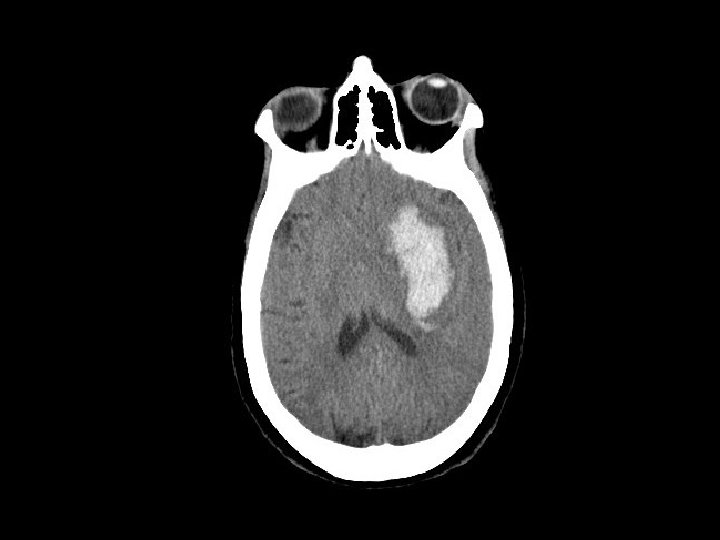

Epidural Hematoma (EDH) • Hemorrhage “above” the dura – Usually arterial (middle meningeal artery) but can also be from venous bleeding • CT: convex (lens shaped) area of blood – Bleeding restricted by the dura’s attachment to the skull • 5 -15% of patients with TBI on CT have an EDH

Epidural Hematoma (EDH) • Potentially rapidly expanding with mass effect and uncal herniation (fixed/dilated pupil) – “Awake and then die” • Most EDHs can be observed • EDHs with mass effect require surgical drainage